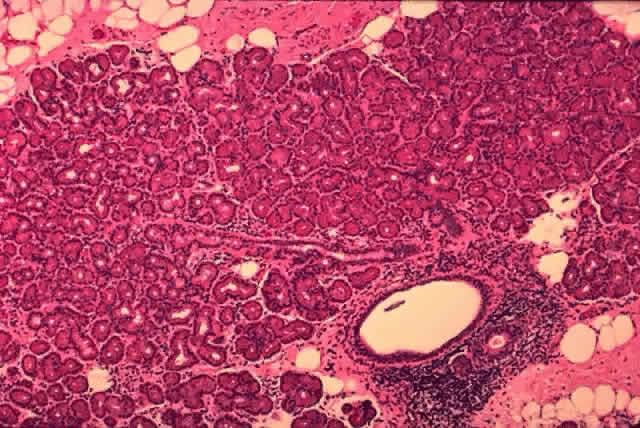

Each lobe of the lacrimal gland is separated into numerous lobules by interlobular fibrovascular connective tissue (Fig. 11). Each lobule, as seen by light microscopy, is composed of two units (Fig. 12): (1) the acinar unit (or secretory unit); and (2) the ductal system. The acinar units are further separated by intralobular fibrovascular connective tissue.

Fig. 12. Lacrimal gland. Each lobule is composed of acinar secretory units (above) and a ductal system. An interlobular duct is seen (lower right). (H & E, original magnification × 25; Courtesy of Ralph Eagle, MD, Philadelphia, PA)

The Ducts

The ducts (Figs. 16 and 17) are branching structures consisting of a central lumen, a luminal cell layer, and a basal cell layer. There are three types of ducts: (1) intralobular ducts, (2) interlobular ducts, and (3) the main excretory ducts. Serous secretion from the acini drain through the small intralobular ducts, then through the larger interlobular ducts, and eventually into the main excretory ducts of the lacrimal glands before draining into the superior lateral aspect of the conjunctival fornix.